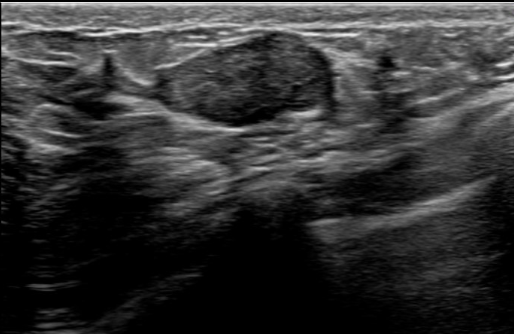

| 超音波(エコー) | 痛みも被曝もなく、若い方にも適しています。つるっとした横長の楕円形に映ることが多いです。 |